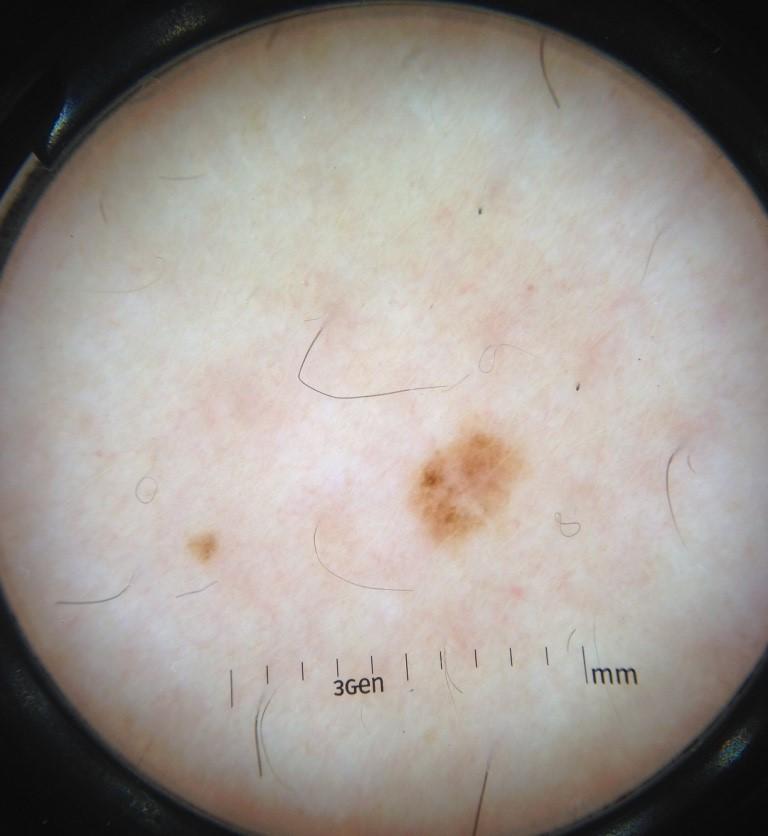

Skin lesion datasets provide essential information for understanding various skin conditions and developing effective diagnostic tools. They aid the artificial intelligence-based early detection of skin cancer, facilitate treatment planning, and contribute to medical education and research. Published large datasets have partially coverage the subclassifications of the skin lesions. This limitation highlights the need for more expansive and varied datasets to reduce false predictions and help improve the failure analysis for skin lesions. This study presents a diverse dataset comprising 12,345 dermatoscopic images with 40 subclasses of skin lesions, collected in Turkiye, which comprises different skin types in the transition zone between Europe and Asia. Each subgroup contains high-resolution images and expert annotations, providing a strong and reliable basis for future research. The detailed analysis of each subgroup provided in this study facilitates targeted research endeavors and enhances the depth of understanding regarding the skin lesions. This dataset distinguishes itself through a diverse structure with its 5 super classes, 15 main classes, 40 subclasses and 12,345 high-resolution dermatoscopic images.

Yilmaz, A., Yasar, S.P., Gencoglan, G. et al. DERM12345: A Large, Multisource Dermatoscopic Skin Lesion Dataset with 40 Subclasses. Sci Data 11, 1302 (2024). https://doi.org/10.1038/s41597-024-04104-3